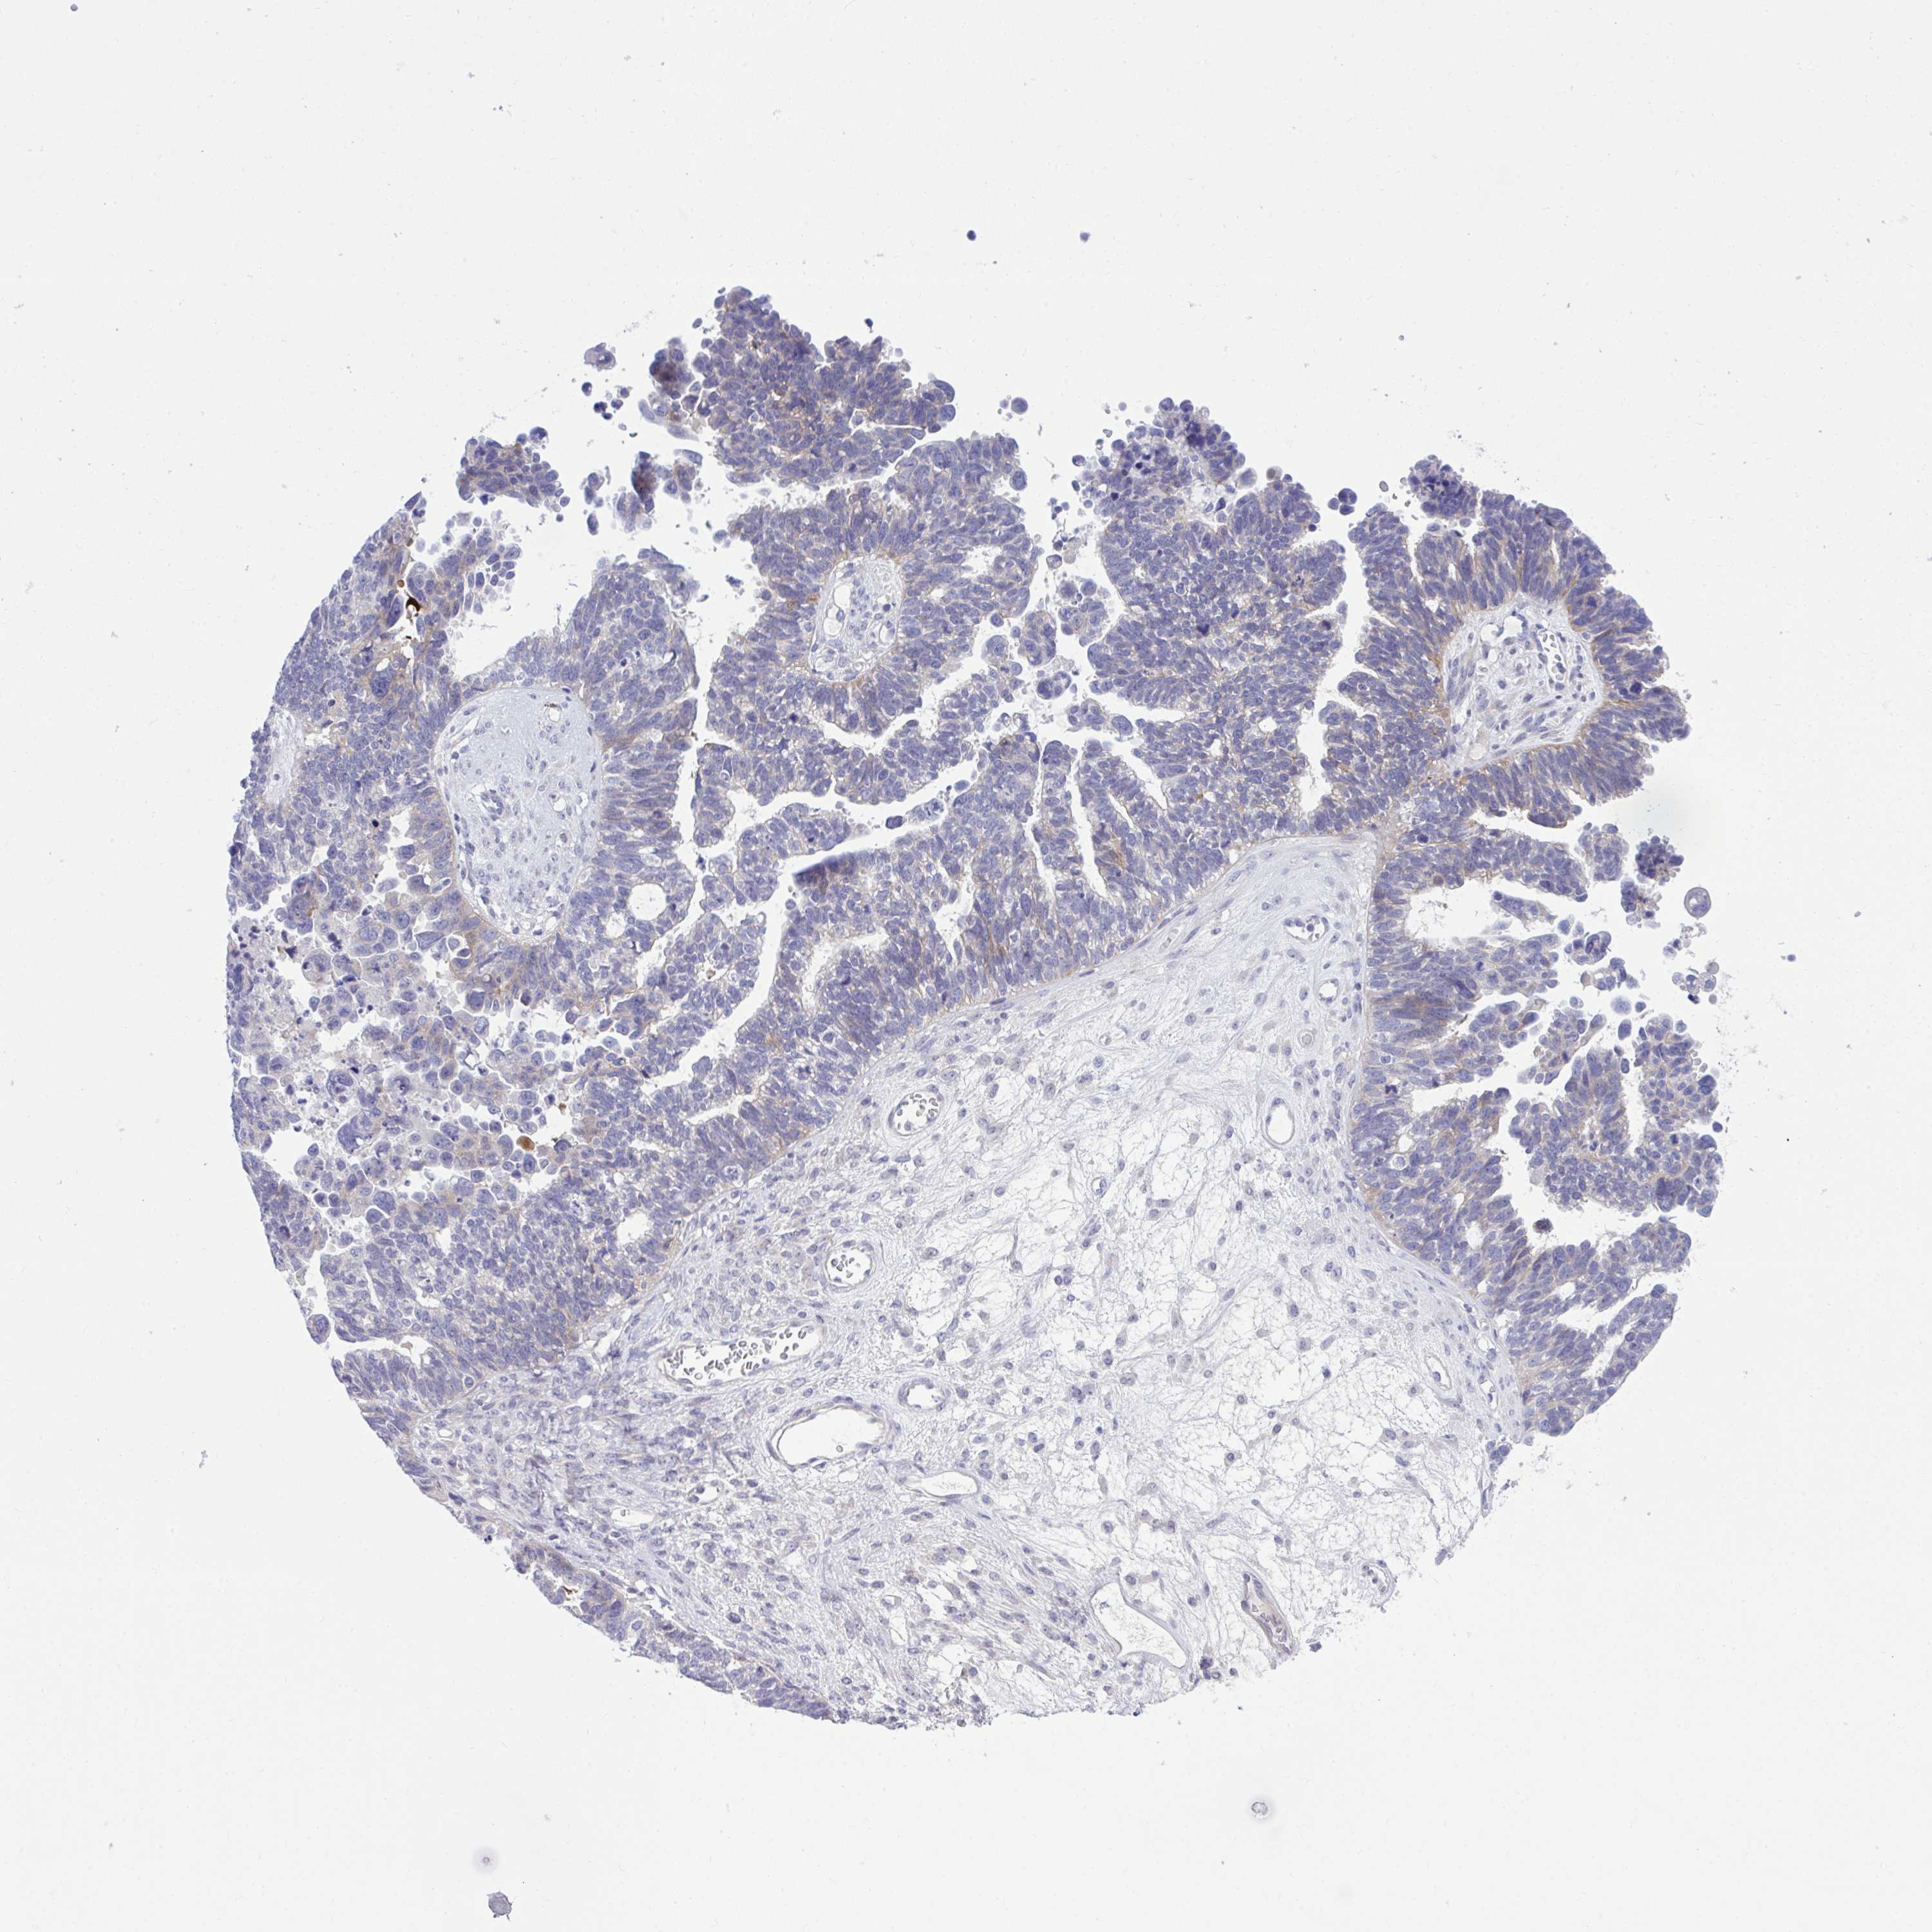

OVARIAN CANCER - Protein expressioni

A mouse-over function shows sample information and annotation data. Click on an image to view it in a full screen mode. Samples can be filtered based on level of antibody staining by selecting one or several of the following categories: high, medium, low and not detected. The assay and annotation is described here.

Note that samples used for immunohistochemistry by the Human Protein Atlas do not correspond to samples in the TCGA dataset.

Antibody stainingi

Antibody staining in the annotated cell types in the current human tissue is reported as not detected, low, medium, or high, based on conventional immunohistochemistry profiling in selected tissues. This score is based on the combination of the staining intensity and fraction of stained cells.

Each image is clickable and will lead to virtual microscopy that enables deeper exploration of all samples and also displays staining intensity scores, fraction scores and subcellular localization as well as patient and tissue information for each sample.

Antibody HPA056415

Staining

High

Medium

Low

Not detected

Intensity

Strong

Moderate

Weak

Negative

Quantity

>75%

75%-25%

<25%

None

Location

Nuclear

Cytoplasmic/membranous

Cytoplasmic/membranous,nuclear

Cystadenocarcinoma, serous, NOS

Cystadenocarcinoma, mucinous, NOS

Carcinoma, endometroid